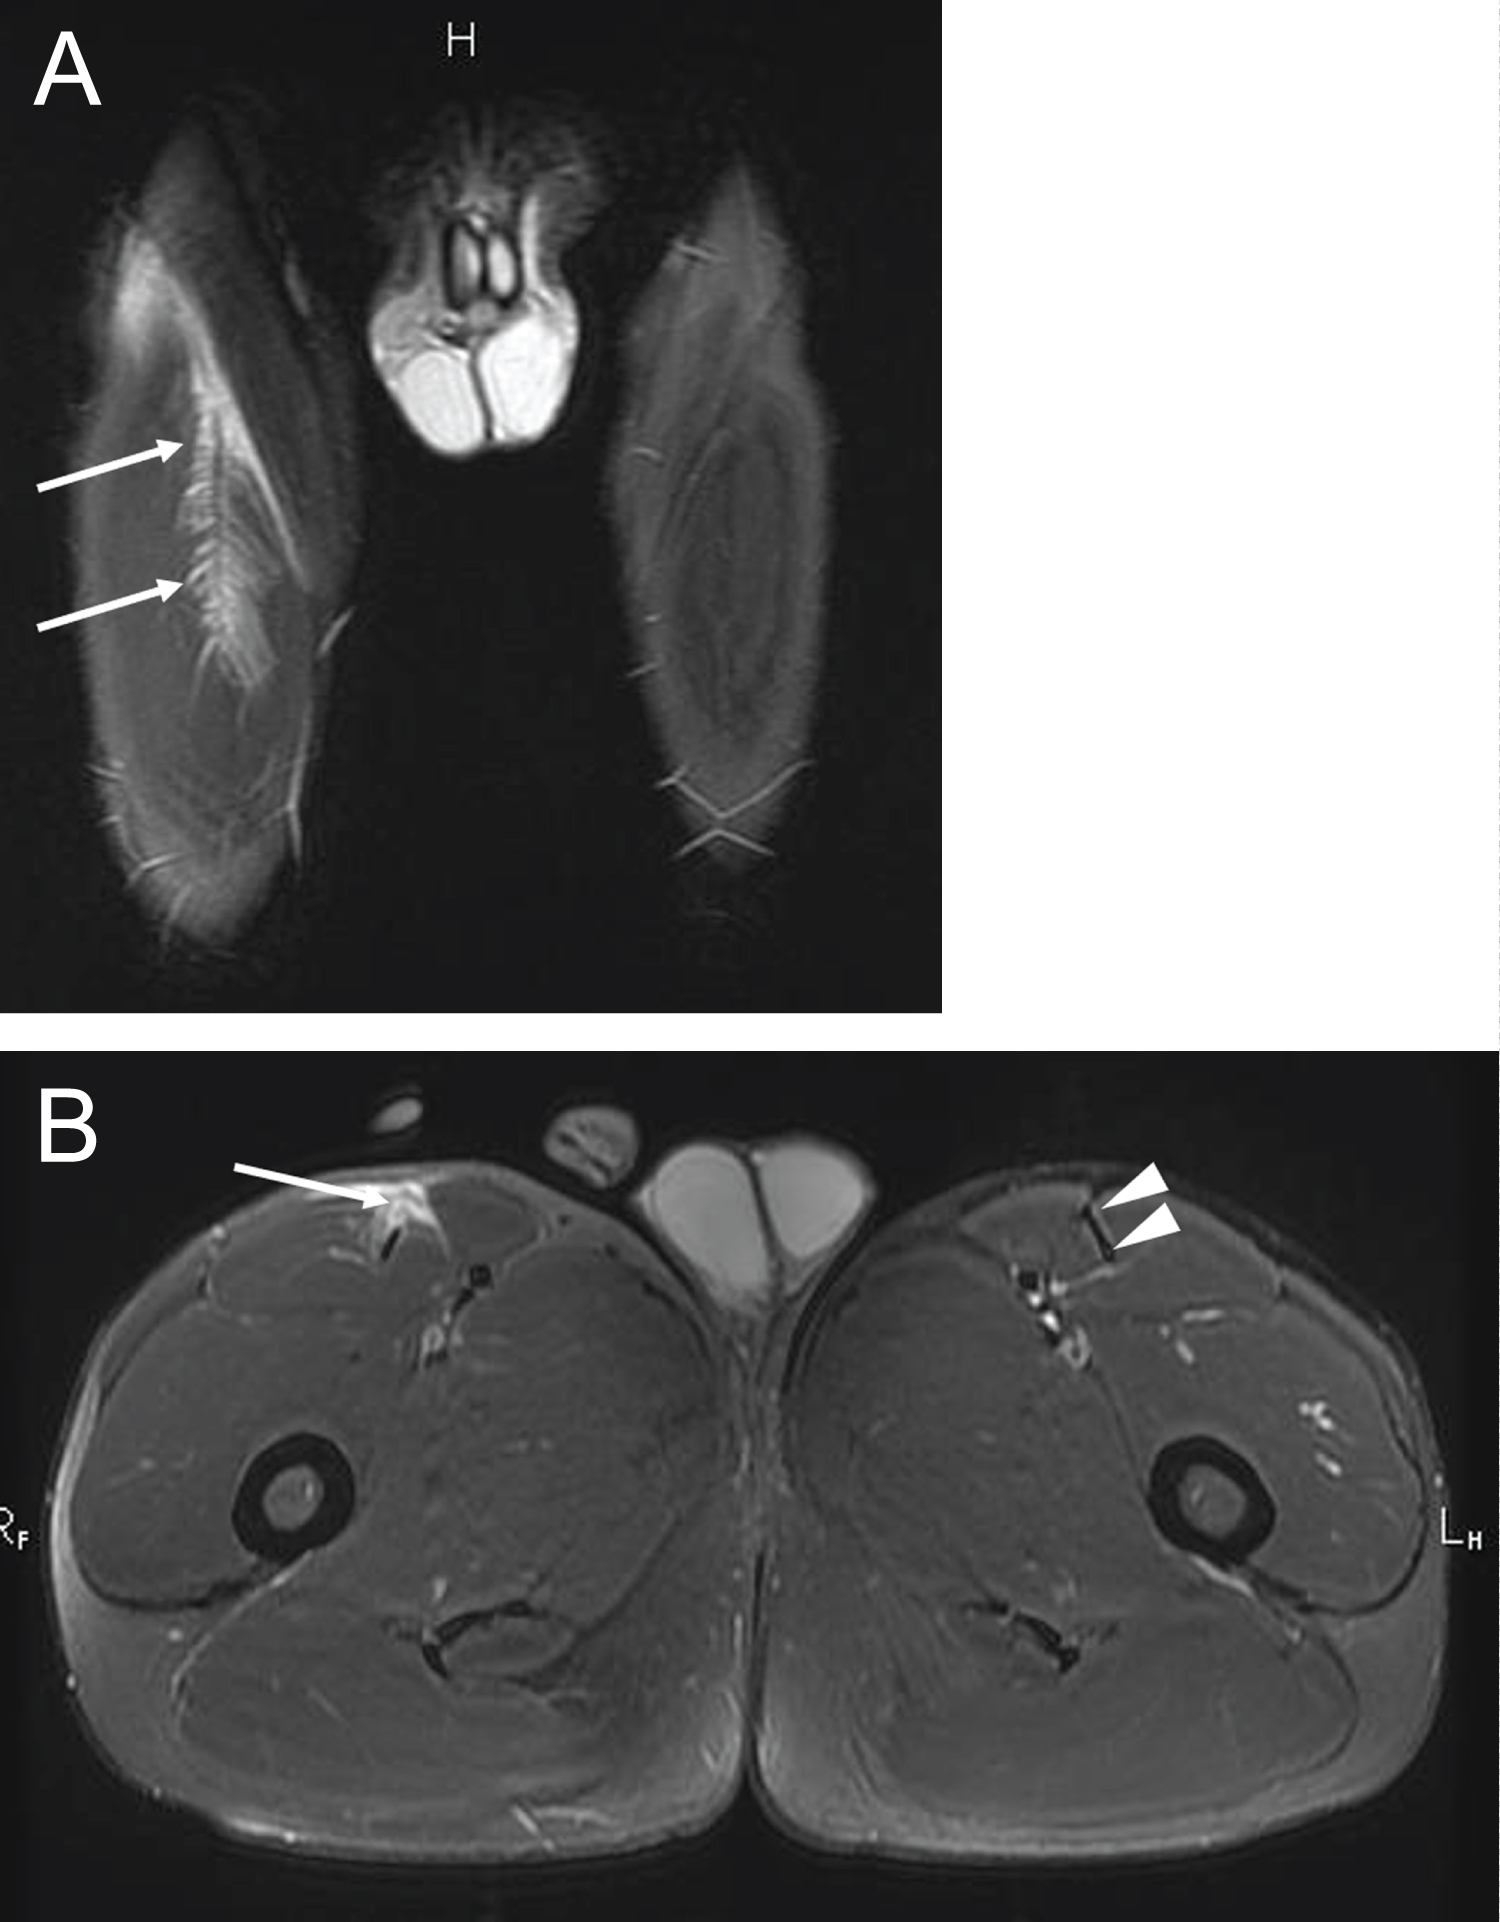

Most injuries depicted on MRI were grade 1 (N = 15; 43%), of which 4 affected the biceps femoris. Twelve muscle injuries were grade 2 (34%), of which 4 affected the biceps femoris and 3 affected rectus femoris (Figure 1). Two muscle injuries were grade 3 (6%) affecting biceps femoris and rectus femoris. Six injuries did not fit into any of above categories (2 cases of chronic musculotendinous junction scarring, one case of incomplete assessment of severity due to signal abnormality extending beyond the field of view, and three cases of delayed onset of muscle soreness with symptoms being observed 48 hours after competition [17]).

Figure 1: Para athlete participating in short distance sprinting (a) Coronal T2-weighted fat-suppressed image shows ill-defined feathery edema (high signal intensity) at the myotendinous junction of the right rectus femoris muscle (arrows); (b) Axial T2-weighted fat-suppressed sequence demonstrates partial rupture of the anterior aspect of the intramuscular tendon (arrow). Note the normal intramuscular tendon at the same anatomical location on the left (arrowheads). This injury was consistent with modified Peetrons grade 2 and BAMIC grade 3c. View Figure 1